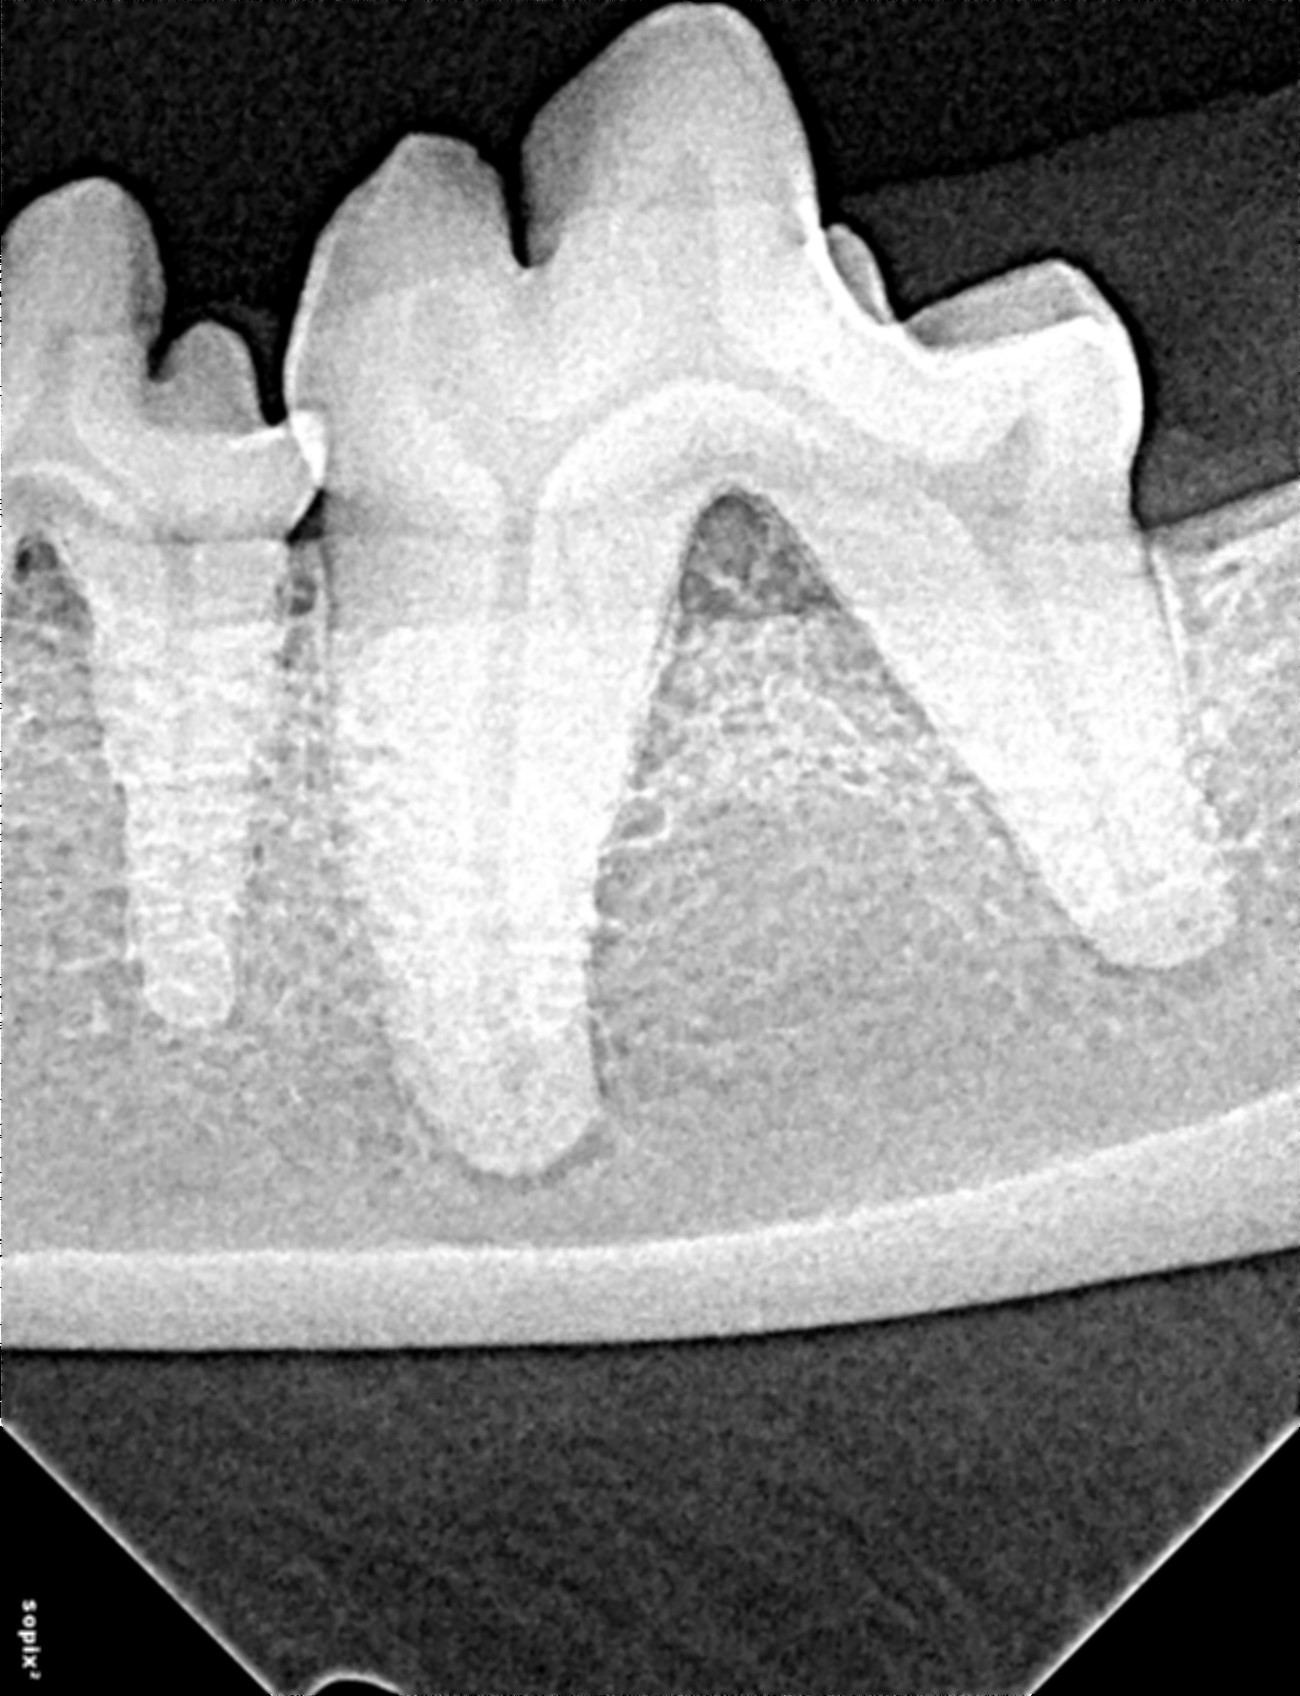

Dental radiographs using Sopix2 digital sensor of 309 showed horizontal alveolar bone loss (Figure 3).

Figure 3. Radiograph 309 showing horizontal bone loss and furcation exposure